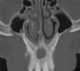

Periapical mixed-radiopacity jaw lesion

Mixed-radiopacity jaw lesion

May Be Caused by